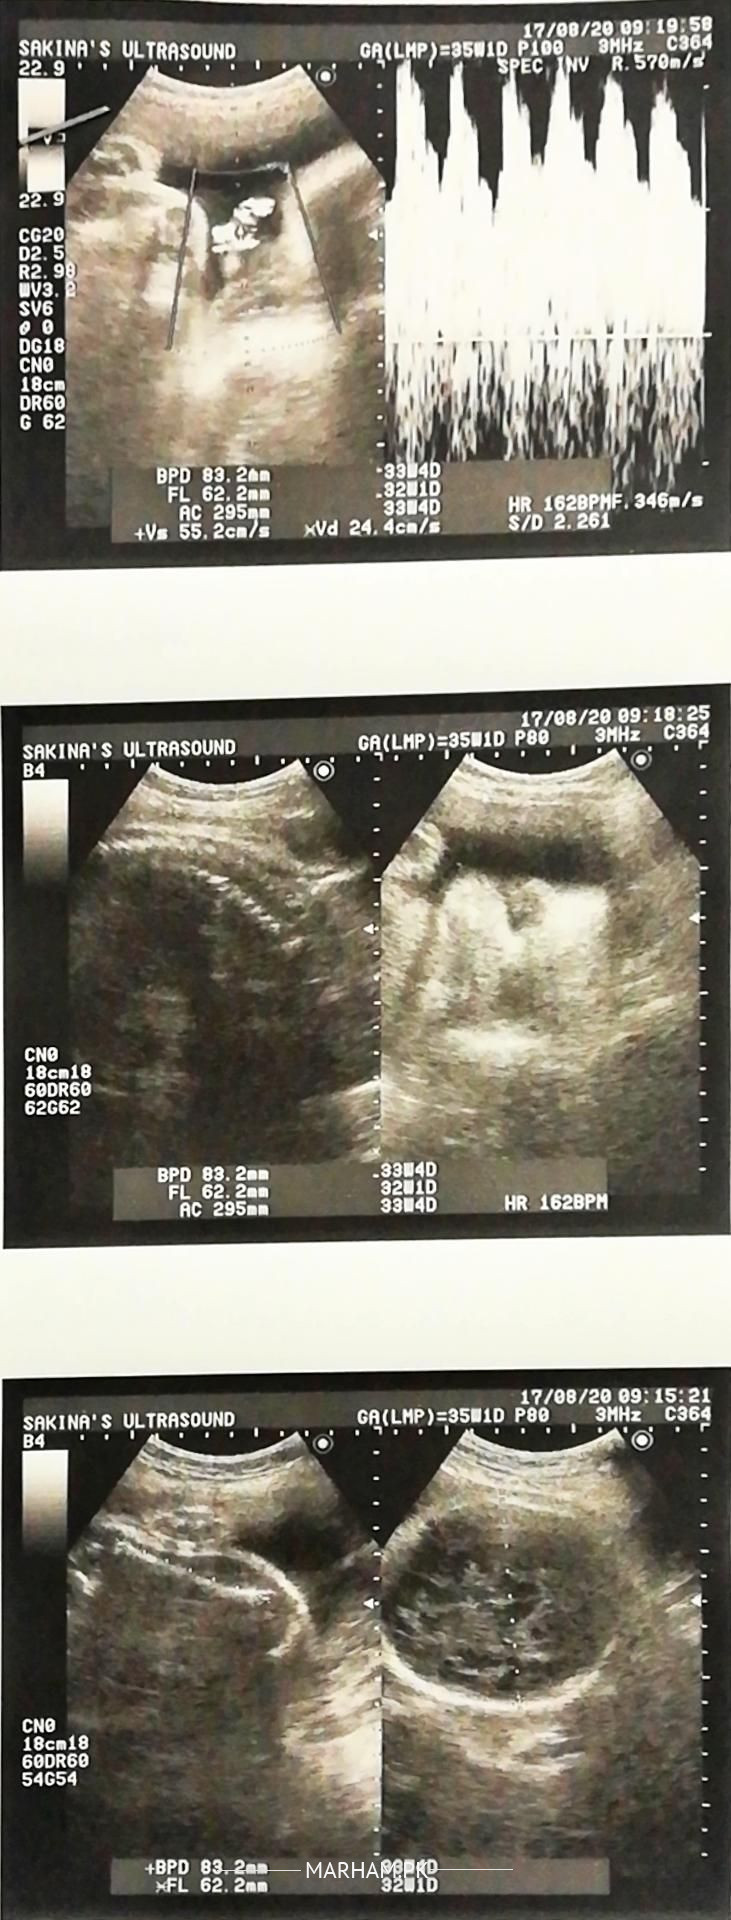

Plz see my wife's report. Docror said that the baby is not growing with normal pace. She is givong us signs of possible c section. We have shown this report to many other doctors in canada and pak and everyone said baby is growing normal. Plz help should we change the doc or go for c section.

follow AFI. if it gets below 5, then its worrisome. for now, the report is normal

report to theek hi lagtihy hy aap ki wife ki kuch detail history chahye

She is 30. Weight was 40 before pregnancy. Now 54kg after 8 months. Had hyper thyroid and PCOs but got ok after pregnancy. All tests including thyroid are ok.

What's her last periods date and send me any early preg scan done